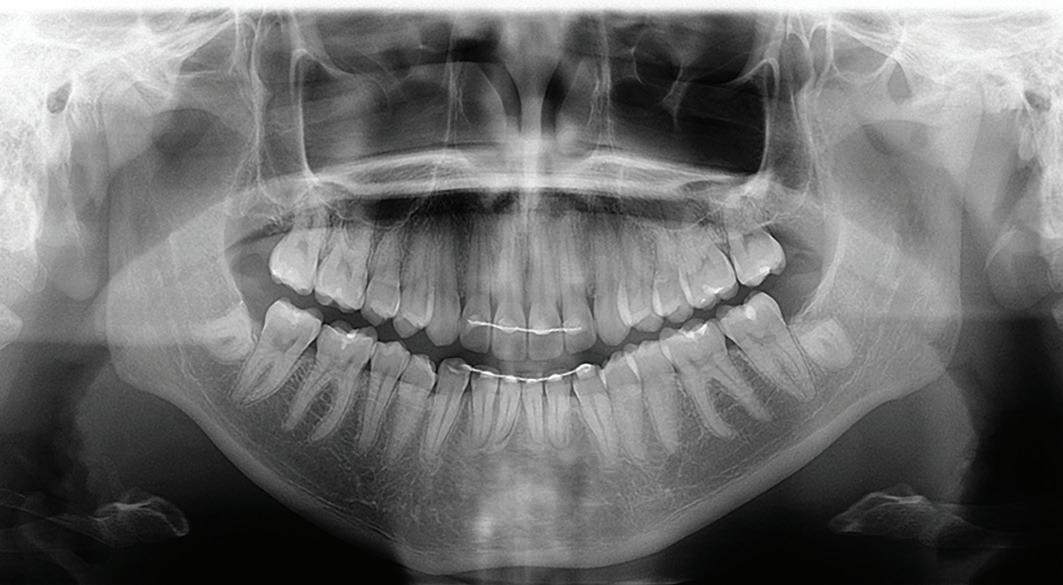

Multidisciplinary approach to diagnosis and management of lymphadenopathy in a patient with mucous membrane pemphigoid: a case report

Heba Turkstani

Eric T. Stoopler

Temitope T. Omolehinwa

Eman Alamodi

Mel Mupparapu